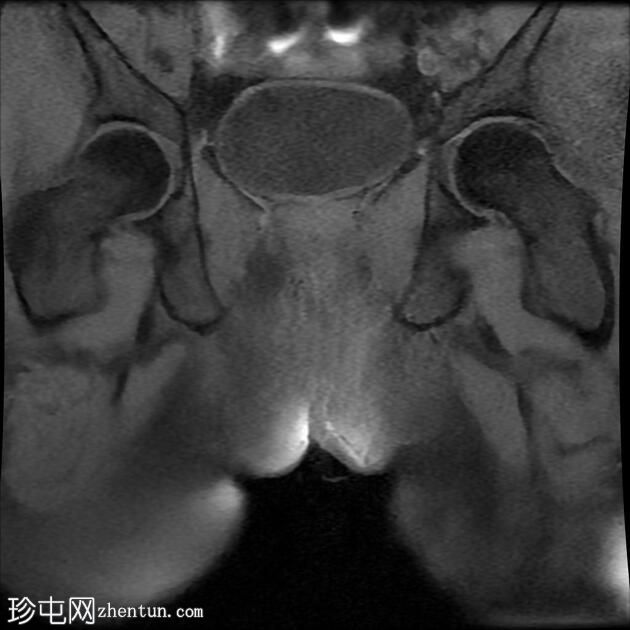

MRI

冠状位T1

脂肪饱和度

冠状位

T2

冠状位T2

一条68毫米厚的强化通道始于左侧肛周区域,向上穿过肛门内外括约肌,在2点钟方向开口于肛管。

无脓肿形成。

MRI成像特征与所述左侧经括约肌肛周瘘相符。